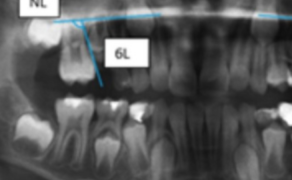

Agenezja drugich zębów przedtrzonowych stanowi jedną z najczęściej występujących wad rozwojowych uzębienia i jest istotnym problemem diagnostycznym oraz terapeutycznym w praktyce stomatologicznej. Prawidłowe rozpoznanie tej anomalii bywa utrudnione, szczególnie u pacjentów w wieku rozwojowym, dlatego wymaga kompleksowej oceny, wykraczającej poza analizę samego wieku chronologicznego. Kluczowe znaczenie ma uwzględnienie stopnia rozwoju zębów sąsiednich, z którymi rozwój drugich zębów przedtrzonowych pozostaje w [...]